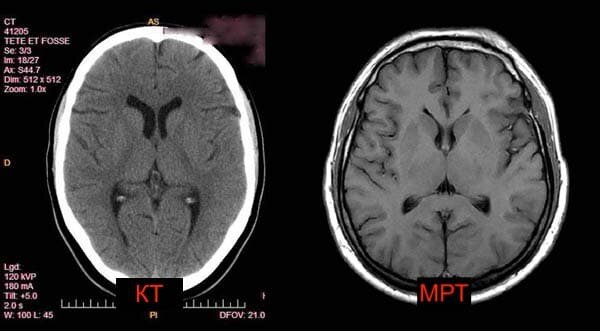

Какой метод диагностики - КТ или МРТ выбрать врачу при сотрясении головного мозга сильно зависит от того, как была получена травма, и как мозг человека в каждом индивидуальном случае отреагировал на удар. В большинстве случаев сразу после сотрясения или при потере сознания пациентом невролог скорее всего назначит компьютерную томографию головного мозга. Её можно сделать пациенту быстро, и она сразу даст ответ на критические для доктора вопросы:

• есть ли перелом пластин черепа

• есть ли угроза кровоизлияния и гематомы мозга.

А вот чтобы оценить состояние вещества и сосудистого русла головного мозга, а также проследить динамику после сотрясения головного мозга, МРТ головного мозга будет наиболее подходящим видом диагностики.

ПОКАЗЫВАЕТ ЛИ МРТ И КТ СОТРЯСЕНИЕ ГОЛОВНОГО МОЗГА

Как правило, при подозрении на сотрясение головного мозга используют как МРТ, так и КТ. Эти два принципиально разных вида томографии в сумме смогут показать полную картину того, что случилось с головным мозгом человека при травме, и каких последствий следует ожидать. КТ при сотрясении головного мозга поможет оценить состояние всех костных структур черепной коробки и ответить на вопрос, есть ли черепные трещины и переломы в результате удара. Также компьютерная томография четко покажет угрозу возникновения кровоизлияния, если сосуды головы были повреждены при сотрясении. МРТ после сотрясения головного мозга даст исчерпывающую информацию о состоянии вещества головного мозга и сосудистого русла. Она также будет использоваться доктором как ежегодная контрольная форма обследования, чтобы наблюдать за состоянием головного мозга после травмы. Следует помнить, что в отдельных случаях симптомы сотрясения головного мозга могут развиваться довольно медленно, и дегенеративные изменения в мозгу случаются через несколько месяцев или лет после момента удара. Иногда сотрясение головного мозга может возникнуть, когда не было прямого сильного воздействия на голову. Такие травмы обладают едва заметными симптомами, но могут приводить к гораздо более серьезным последствиям. Особенно, если это происходит неоднократно. Как пример можно взять футболистов, которым часто приходится принимать мяч головой. При помощи диффузионной МРТ во время исследования 2013 года ученые оценивали, какое влияние игра оказала на мозг футболистов.